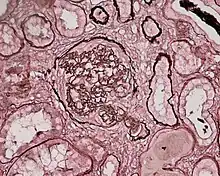

Glomerulonephritis (GN) is inflammation in the kidney.[1] It typically presents with blood and protein in urine.[2] Complications may include high blood pressure and kidney failure.[2]

Generally, the endothelial and mesangial cells in the endocapillary compartment of the glomeruli are involved.[2]